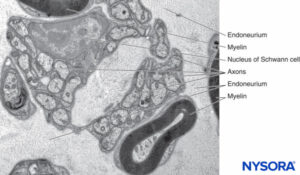

ENDONEURIUM

The endoneurium (Figures 7 and 8) intimately surrounds Schwann cells and fills the space bounded externally by the perineurium. Endoneurium contains collagen fibers, fibroblasts, capillaries, and a few mast cells and macrophages. Collagen fibers are permeable and concentrated in a zone beneath the perineurium and around nerve fibers and blood vessels. The collagen fibers surround both myelinated and unmyelinated nerve fibers. However, the endoneurial sheaths around smaller myelinated fibers and around some unmyelinated axons are less well organized (Figure 9).

FIGURE 9. Unmyelinated and myelinated axons enclosed by endoneurium. Transmission electron microscopy. Magnification ×20000. (Reproduced with permission from Reina MA, Arriazu R, Collier CB, et al: Electron microscopy of human peripheral nerves of clinical relevance to the practice of nerve blocks. A structural and ultrastructural review based on original experimental and laboratory data. Rev Esp Anestesiol Reanim. 2013 Dec;60(10):552-562.

Mast cells are especially numerous along the course of blood vessels. Mast cell granules are soluble in water and are therefore not easily revealed in sections routinely prepared with hematoxylin and eosin stain. After adequate fixation, the granules stain with most basic dyes and become metachromatic after certain dyes, such as toluidine blue. Electron microphotographs show that the secretory granules are membrane bound, and the granule matrices have varying densities and characteristic helical-type patterns (Figure 10). Macrophages are also found frequently around perivascular endoneurium (Figure 11). The endoneurium contributes to the stability of the internal medium where the Schwann cells and axons are located. The endoneurium of cutaneous nerves contains more collagen fibers than deep nerves; this probably is related to its protective role. The endoneural collagen is believed to originate from the Schwann cells, which are 9:1 more prominent than fibroblasts. Schwann cells represent 90% of intrafascicular cells, whereas fibroblasts account for less than 5% of the remaining number. The endoneurium along with the epineurium and perineurium contribute to nerve protection against elongation under strain. The sinuous trajectories of axons confer additional protection on nerves. Endoneurial sheaths around axons is demonstrated in figures 7, 8 and 9. Instead of individually shaped endoneurial layers, the endoneurium appears rather as a continuum, forming several canaliculi into which axons are embedded.